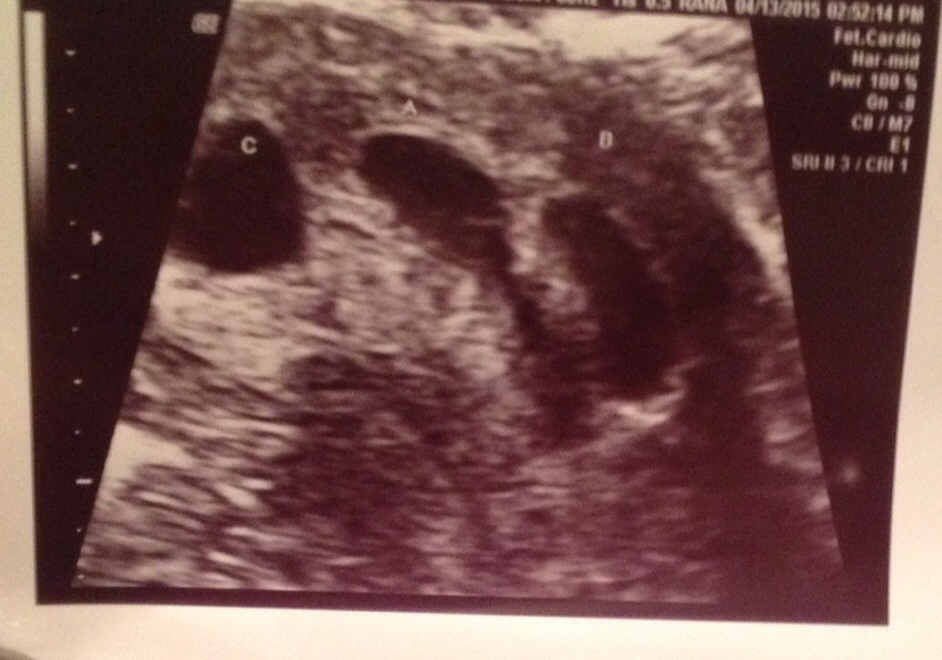

Just came from ultra sound...and I had one at 5 weeks an seen one empty sac so was worried about going today an omg got a shocker that's for sure triplets!!! I've been posting how I haven't had symptoms so nothing has mentally prepared me for this I'm still laughing!!

• 8w3d but that puts us at nov 20 but I may get bumped to an October board down the road

8w3d